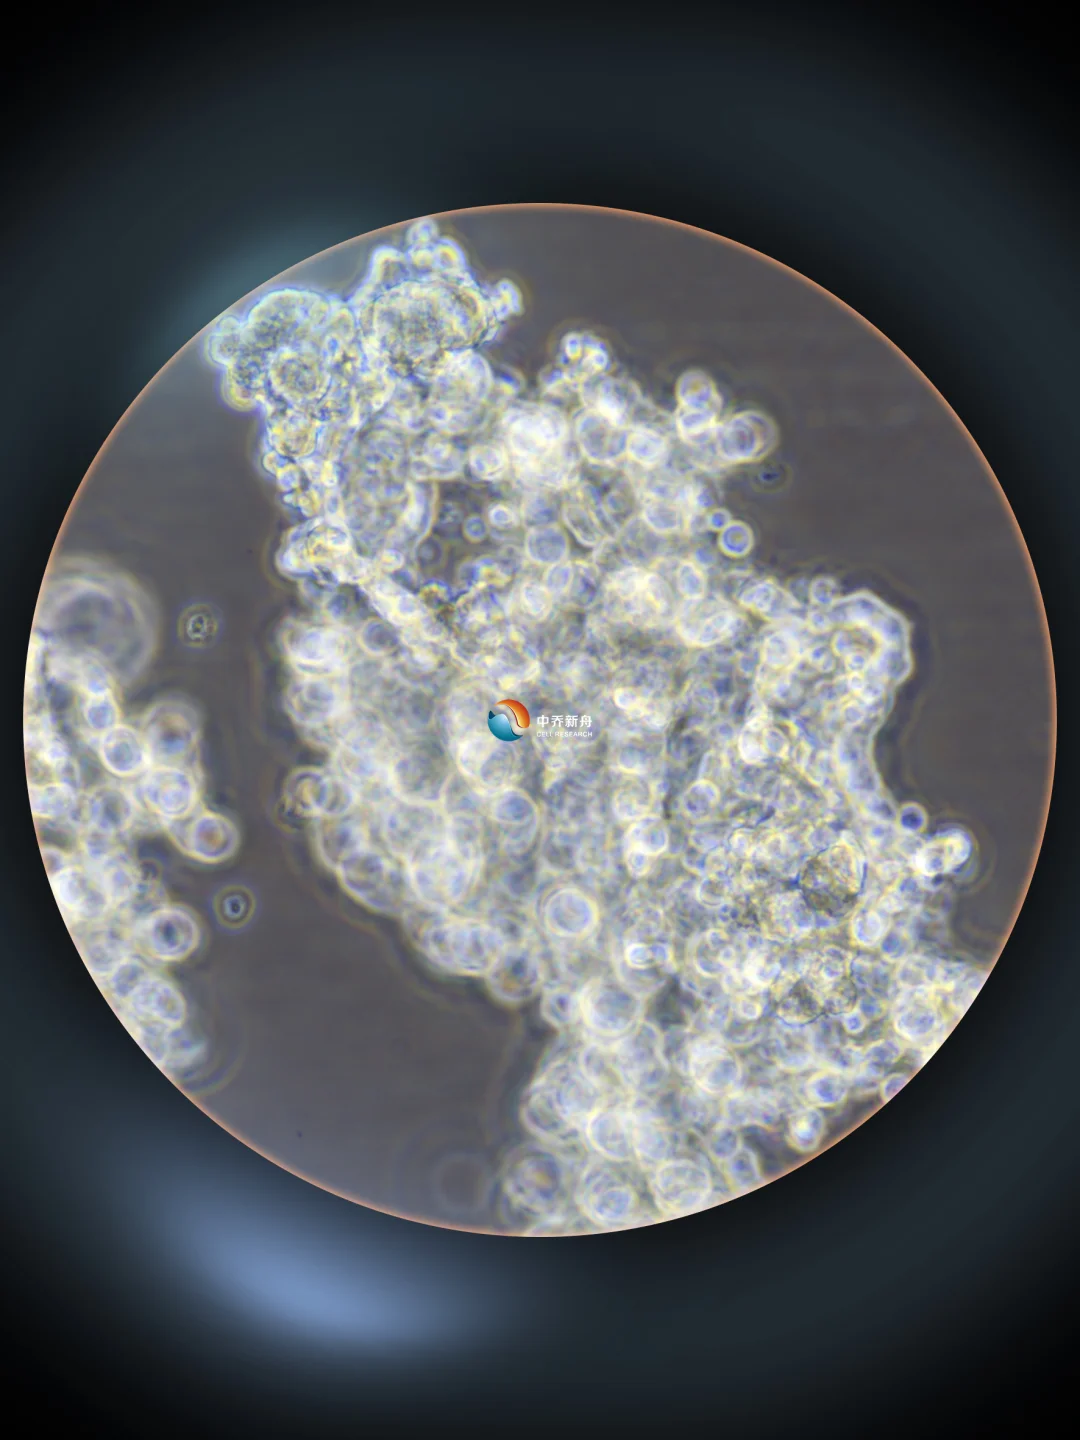

SCLC-2(SMC) 4X、10X、20X细胞影像实拍画面。 1.该细胞生长状态为团块状悬浮生长,生长过程中会持续产生较多细胞碎片; 2.收到复苏好的细胞后如果细胞碎片、黑色杂质较少,则不需要理会,建议加适量培养液将细胞分装到3-4个培养瓶继续培养; 3.若细胞碎片和杂质较多,可以用沉降法去除(将细胞悬液转移到15ml离心管中,静置数分钟,直到活的细胞团块沉降到离心管底部,吸掉上清液更换新鲜培养即可。这个办法可以去除大部分较小的细胞碎片。)后加适量培养液并分装到3-4个培养瓶。